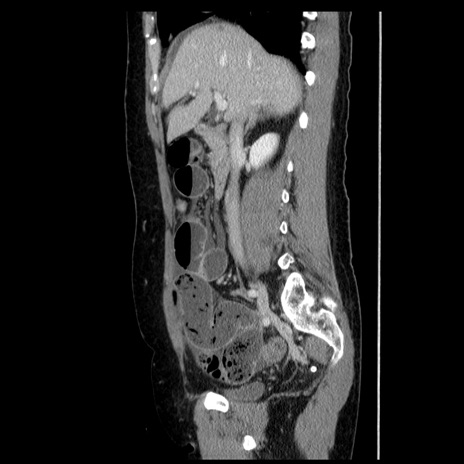

症例6(矢状断像)

【症例】50歳代女性

【主訴】下腹部痛

【既往歴】卵巣癌術後(8年前に当院で卵巣摘出)

【身体所見】 意識清明、腹部:平坦、腸蠕動音→、やや硬、下腹部自発痛・圧痛あり、反跳痛あり、筋性防御なし。